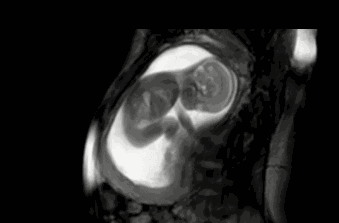

胎儿是很聪明的,一般从怀孕四个月起,胎儿就有了敏感的听觉,所以孕中期可以开始做胎教,刺激胎儿的听觉神经发育。

胎儿的听觉系统在孕期就已经发育,胎儿在孕六个月的时候,能听到外界的声音,包括妈妈的说话声,呼吸声。所以,孕期做胎教还是很有必要的,而且胎儿能感觉到,但并不一定能完全理解胎教中的全部意思。

我是二胎妈妈,孕期6个月的时候就明显感觉到胎宝宝对声音很敏感。每次播放胎教音乐的时候,胎儿就会随着音乐动起来,可以感觉到宝宝很兴奋。原来,4个月的时候胎儿听觉器官已初步发育完全,但对接收外界声音还是比较模糊,但到了第6 个月时,胎宝宝的听力就与成人无异了,真的是神奇。

视觉胎教,宝宝23周后,就能感受到外界的光刺激。但是频繁照射反而对宝宝的生长不利。